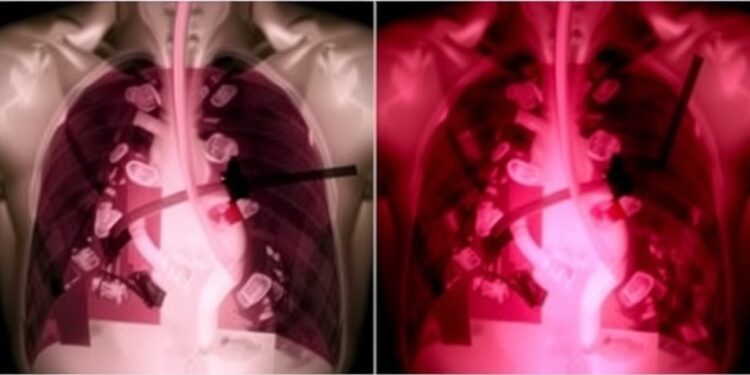

In the realm of thoracic surgery, the modalities of postoperative care are continuously evolving to improve patient outcomes. One recent study sheds light on the comparative efficacy of two prevalent types of chest drains following video-assisted thoracoscopic surgery (VATS) lobectomy. This investigation juxtaposed the coaxial silicone (SIL) drains against the traditional polyvinyl chloride (PVC) drains, focusing particularly on their impact on postoperative pain, drainage efficacy, and overall treatment results within a defined timeframe.

Chest drains are commonly utilized in thoracic surgery to facilitate the evacuation of fluid and air from the pleural space post-surgery. The choice of drain can significantly influence a patient’s postoperative experience, encompassing pain management and recovery speed. This randomized prospective study comprised a total of 80 patients, all diagnosed with lung cancer, who underwent VATS lobectomy between September 2020 and June 2023. A meticulous randomization process ensured that participants were divided equally into two groups, thereby allowing for an equitable comparison of the two drain types.